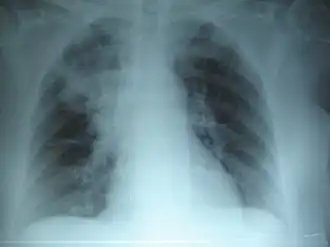

Radiografía de tórax de una neumonía causada por influenza y Haemophilus influenzae, con consolidaciones parcheadas, principalmente en el lóbulo superior derecho (flecha).